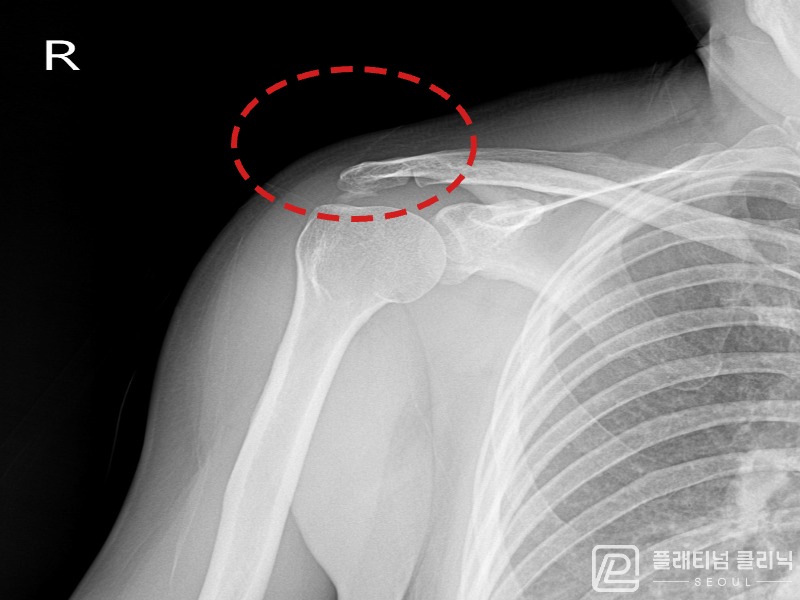

[촬영시기:21.11.04~21.11.09]

[석회분쇄흡입술] 우측 어깨 극심한 야간 통증으로 수면이 불가능해진 50대 여성 환자로, X-ray에서 우측 극상근건 내 석회 침착이 확인되어 석회분쇄흡입술을 시행하였습니다.